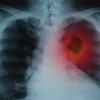

Akciğer dokusundaki normal hücreler kontrol dışı çoğalarak kitle yani tümör oluşturduğunda akciğer kanseri meydana geliyor. Kitle büyüyerek önce çevre dokulara, dolaşım yoluyla da beyin, karaciğer gibi diğer organlara yayılıyor. Akciğer kanserinin erken dönemde belirti vermeyebileceğini ifade eden Göğüs Hastalıkları Uzmanı Dr. Aygün Gür, “Geçmeyen ve giderek artan öksürük, öksürükle ağızdan kan veya kanlı balgam çıkarmak, nefes darlığı, göğüs ağrısı, ses kısıklığı, halsizlik, iştahsızlık, geçmeyen ve tekrarlayan akciğer enfeksiyonu gibi belirtiler görülebilir.” dedi.

Tanı için akciğer röntgeni, bilgisayarlı tomografi gibi görüntüleme yöntemleriyle kitle saptandıktan sonra, kitleye hangi yolla ulaşarak örnek alınacağı belirleniyor. Kanserin türü ve evresi belirlendikten sonra tedavinin planlandığını belirten Gür, “Akciğer kanserinde erken tanı çok önemli. Tedavi şansını artırdığı gibi ölüm oranını da azaltmaktadır. Tedavi; hastanın yaşı, klinik durumu, kanserin tipi, evresi gibi faktörler ışığında planlanarak cerrahi, kemoterapi veya radyoterapi programlarının biri veya birkaçı bir arada uygulanır” diye konuştu.